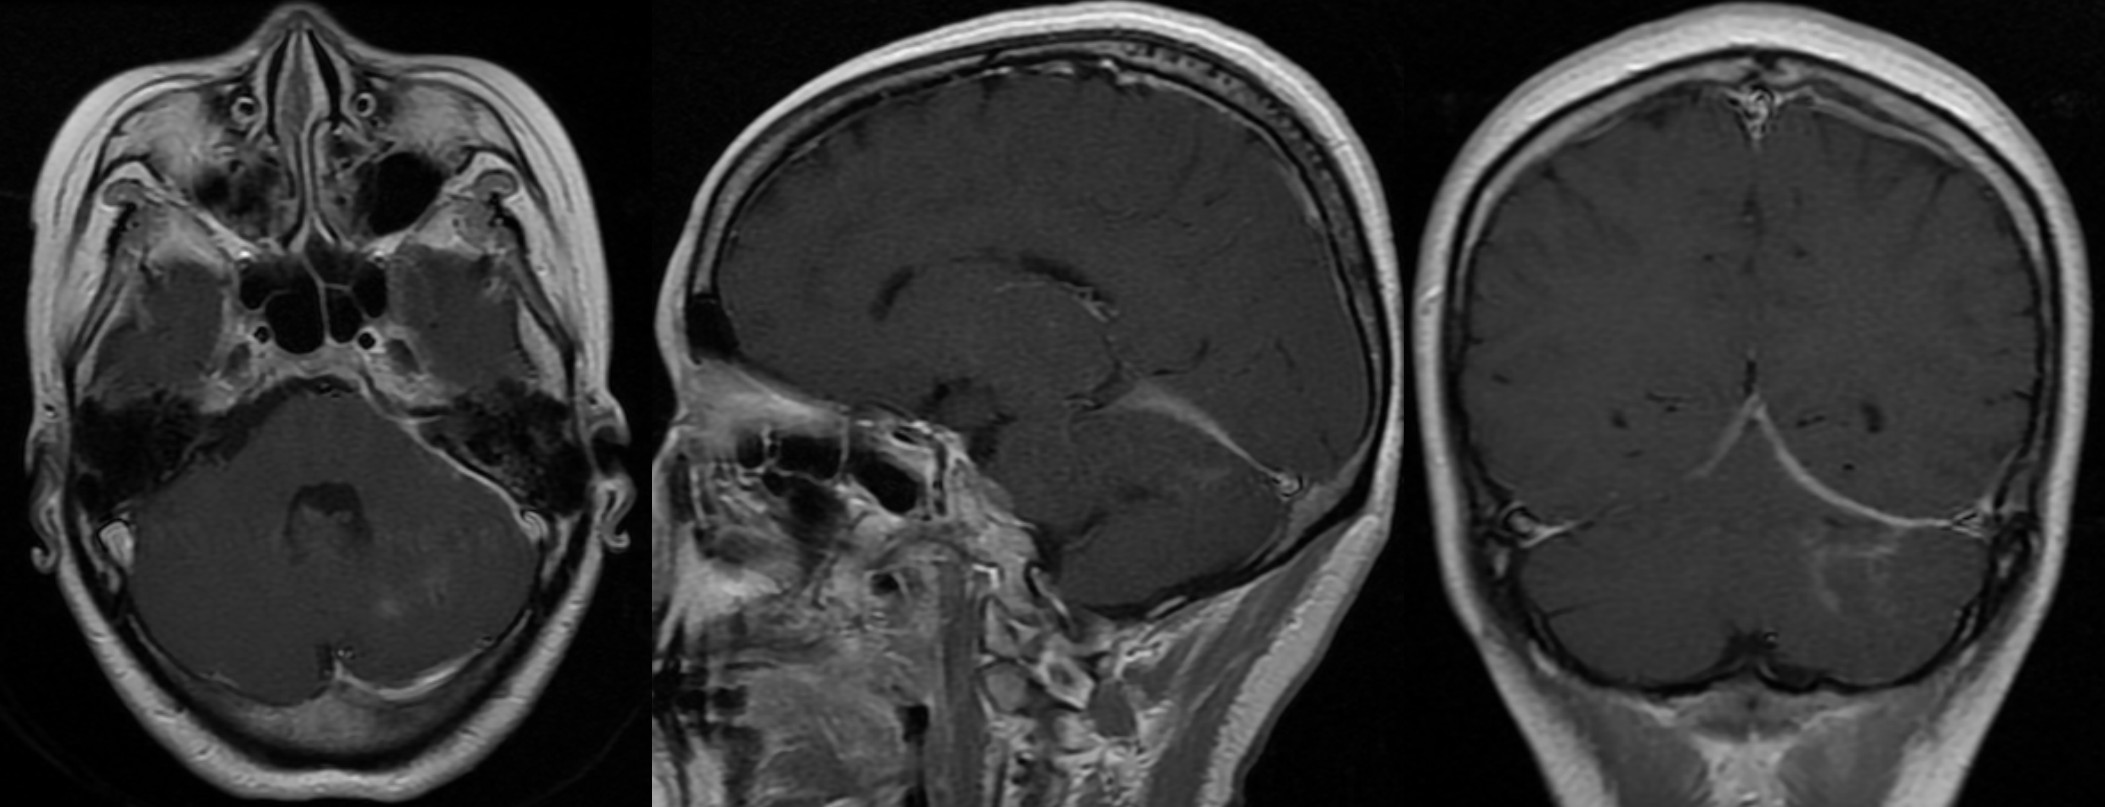

4月20日复查头颅MRI平扫+增强提示脓肿已消失,小脑幕硬膜增厚程度较前明显减轻。